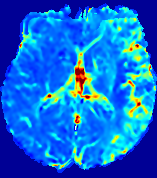

LesionRefer to captionRefer to captionRefer to captionRefer to captionRefer to captionRefer to caption𝐕rgbsubscript𝐕𝑟𝑔𝑏{\bf{V}}_{rgb}Refer to captionRefer to captionRefer to captionRefer to captionRefer to captionRefer to caption𝐕2subscriptnorm𝐕2{\|\bf{V}}\|_{2}Refer to captionRefer to captionRefer to captionRefer to captionRefer to captionRefer to captionRefer to caption3.53.53.52.82.82.82.12.12.11.41.41.40.70.70.70.00.00.0(mm/s)𝑚𝑚𝑠(mm/s)D𝐷DRefer to captionRefer to captionRefer to captionRefer to captionRefer to captionRefer to captionRefer to caption0.0200.0200.0200.0160.0160.0160.0120.0120.0120.0080.0080.0080.0040.0040.0040.0000.0000.000(mm2/s)𝑚superscript𝑚2𝑠(mm^{2}/s)Slice #1Slice #2Slice #3Slice #4Slice #5Slice #6

Figure 3: PIANO feature maps for one stroke patient, where the lesion is located in the left hemisphere. Top row: segmented stroke lesion region (white) on different slices, obtained from ISLES 2017. The corresponding slices for the PIANO feature maps are shown in the following rows.

For a better insight into an estimated velocity field 𝐕𝐕{\bf{V}} and diffusion field 𝐃𝐃{\bf{D}}, we compute the following maps: (1) 𝐕rgbsubscript𝐕𝑟𝑔𝑏{\bf{V}}_{rgb}: Color-coded orientation map of 𝐕=(Vx,Vy,Vz)T𝐕superscriptsuperscript𝑉𝑥superscript𝑉𝑦superscript𝑉𝑧𝑇{\bf{V}}=(V^{x},V^{y},V^{z})^{T}, obtained by normalizing 𝐕𝐕{\bf{V}} to unit length and mapping its 3 components to red, green, blue respectively; (2) 𝐕2subscriptnorm𝐕2\|{\bf{V}}\|_{2}: 222 norm of 𝐕𝐕{\bf{V}}; (3) D𝐷D: scalar field in Eq. 5.

Fig. 3 and Fig. 4 show the PIANO feature maps estimated from two ISLES 2017 patients: all are highly consistent with the lesion in both cases. Details of the blood flow trajectories are revealed in 𝐕rgbsubscript𝐕𝑟𝑔𝑏{\bf{V}}_{rgb} by the ridged patterns and the sharp changes of colors in the unaffected (right) hemisphere, while the flat patterns appearing within the lesion provide little directional information about the velocity and indicate low velocity magnitudes. Velocity magnitudes are more directly visualized via 𝐕2subscriptnorm𝐕2\|{\bf{V}}\|_{2}, from which one can easily locate the lesion where 𝐕2subscriptnorm𝐕2\|{\bf{V}}\|_{2} is low. D𝐷D also indicates lower diffusion values in the lesion, though with less contrast potentially due to the fact that it captures the accumulated effect of CA diffusion at the voxel-level.